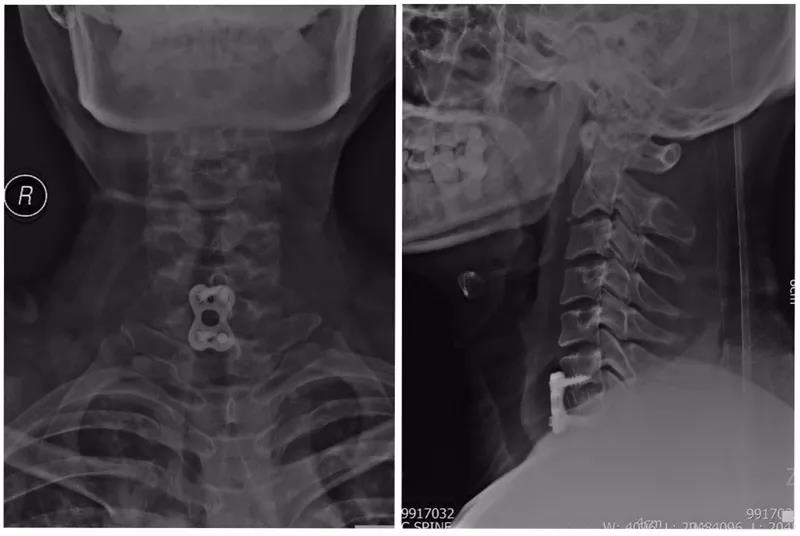

术前X线正侧位片

术前CT

术前MRI

术中完成减压后置入钉棒系统

术中C臂透视